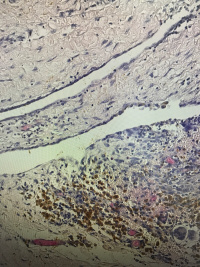

性别年龄40临床诊断

一般病史腹股沟囊性包块,与疝囊壁粘连

标本名称腹股沟包块

大体所见囊实性包块,大小3.8✖️3✖️1.9cm,囊壁厚0.1-02cm

囊性淋巴管瘤?

囊性良性间皮瘤?

有陈旧性出血, 子宫内膜异位也要考虑,问一问病人有没有经期疼痛。

免疫标记对鉴别可能会有所帮助。